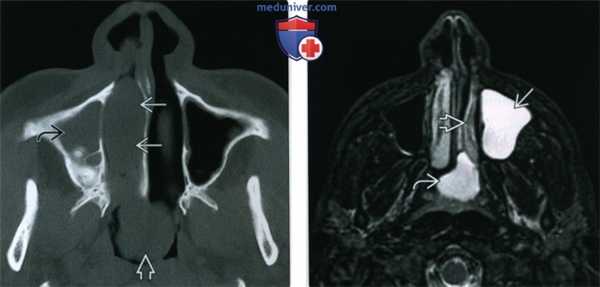

1. Общая характеристика:

• Лучший диагностический критерий:

о Гантелеобразное образование в верхнечелюстной пазухе с тонкой ножкой из воронки/добавочного устья — полость носа

• Локализация:

о Самый частый тип: антрохоанальный полип:

- Солитарное полиповидное образование в верхнечелюстной пазухе, распространяющееся сквозь расширенное устье верхнечелюстной пазухи/воронку или добавочное устье в полость носа:

Большие образования пролабируют через хоаны в носоглотку

• «Костная» КТ:

о Хорошо отграниченное гантелеобразное образование низкой плотности, соответствующей слизи:

- Возникает в верхнечелюстной пазухе, проходит через расширенное устье, в т.ч, добавочное, в полость носа с этой же стороны:

Легкое ремоделирование костей вокруг воронки/добавочного устья в отсутствие деструкции

Ножку или среднюю часть гантели может быть сложно различить на корональной КТ пазух

- Большие полипы пролабируют в носоглотку